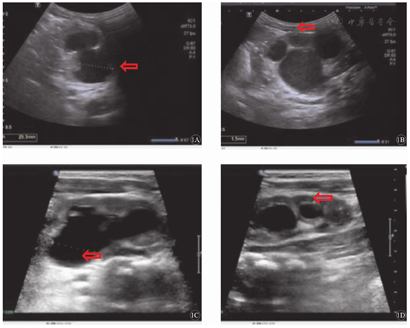

本组16例重度CH患儿中,12例接受外科手术治疗后好转;对19例并发发热性UTI的CH患儿,采取抗菌药物治疗后痊愈,对5例VURⅢ级及以上CH患儿,采取预防性长期口服小剂量抗菌药物治疗,随访结束时,仍在继续治疗中。随访期内,对重度肾积水、肾盂扩张加重和发生相关并发症患儿,采取定期复查尿常规、肾功能、泌尿系统超声,eGFR评估,均提示正常(图1)。

注:CH为先天性肾积水